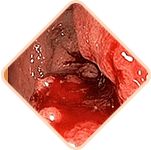

Ellenőrizze magát! Észlelt legalább egy tünetet a következők közül?

Idegen test érzése, nehézségérzés a végbélben.

Viszketés és égő érzés a végbélnyílásnál.

Fájdalom ürítéskor, járáskor és ülő helyzetben.

Az aranyeres csomók fájdalma tapintásra

Vérzés ürítés közben vagy megerőltetés esetén